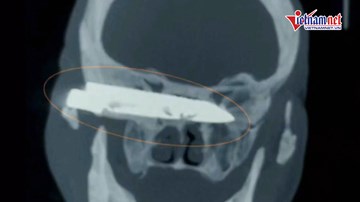

Lấy lưỡi dao dài 10cm nằm trong đầu người đàn ông suốt 26 năm

Một lưỡi dao dài 10cm nằm trong đầu một người đàn ông 76 tuổi suốt 26 năm, đã được các bác sĩ ở Trung Quốc lấy ra thành công